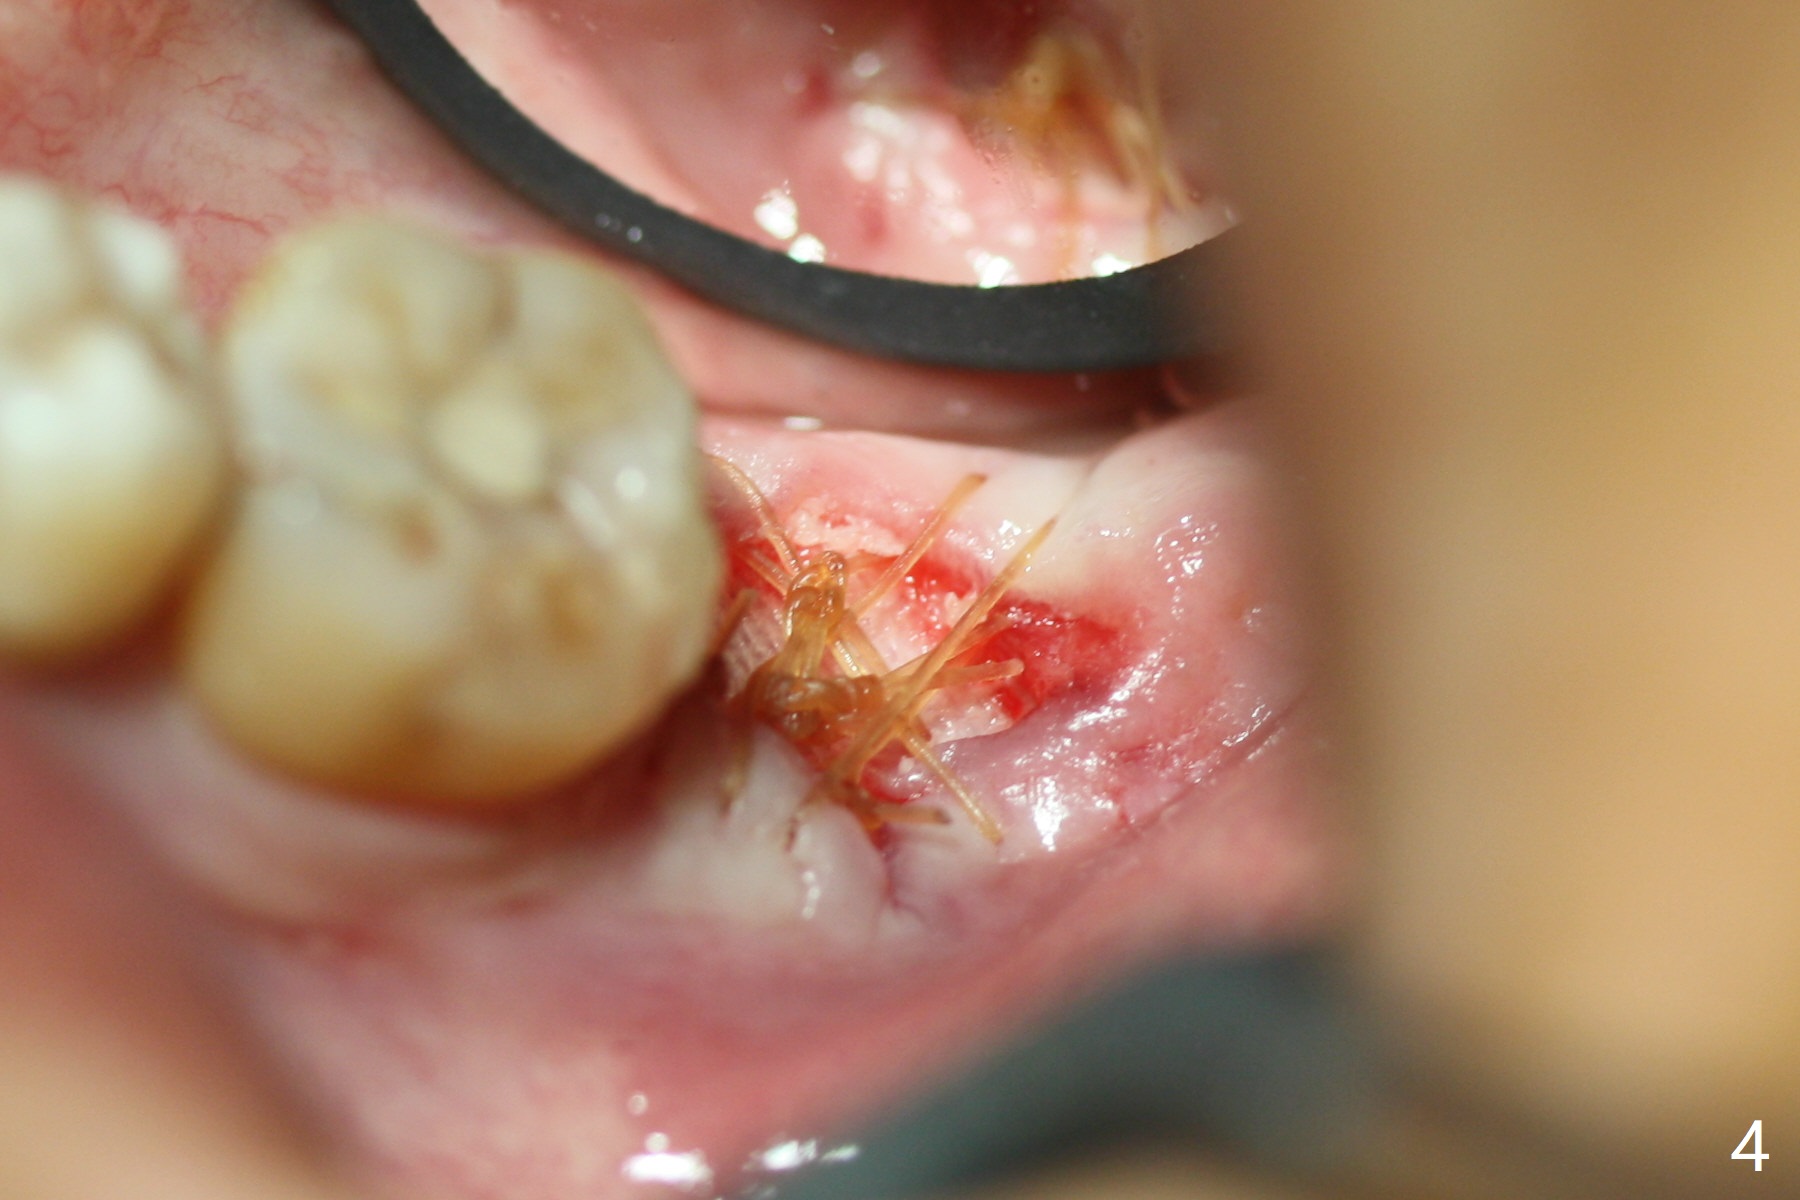

The patient with chronic buccal abscess at #31 is nervous. After extraction, a 7x11 mm tapered implant drops into the single socket, which is close to the Inferior Alveolar Canal (Fig.2). The bottom of the socket is sensitive to manipulation (explorer) after infiltration anesthesia. A 8x14 mm tapered tap is placed without binding, neither is a 8x14 mm cylindrical implant. The implant stability does not increase when Vera (.2-1.0 mm) or Vanilla (.5-1.0 mm) Graft is placed. Socket preservation is finished with Collagen plug and 6-month membrane (Fig.3,4).